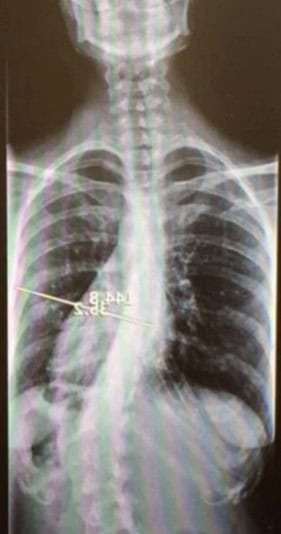

Jak už bylo řečeno, vybočení, nebo postranní zakřivení páteře je u každého člověka jiné. Snímek RTG ukazuje na celkem jasné zakřivení do tvaru písmene C. (Pravá strana obrázku je pravá strana těla). Na pravé straně je prohloubení (concave), na levé straně je vychýlení (convex).

Takže pokud se podíváme na ten RTG snímek, pak vidíme, že svaly na pravé straně jsou zkrácené, příliš napjaté. V napětí jsou ale nejen šikmé břišní svaly, vnitřní i vnější, ale taky quadratus lumborum (kvadratický bederní sval) a psoas, hlavní napřimovač a stabilizátor páteře.

Šikmé břišní svaly jsou velmi silné svaly středu těla (core), které táhnou žebra (hrudní koš) a pánev k sobě, jak je vidět na snímku RTG (pravá strana). Můžete vidět, že vzdálenost mezi posledním dolním žebrem a vrchní hranou pánevní kosti je kratší na pravé straně než na levé. Můžete taky vidět, že bok na pravé straně směřuje víc nahoru než na levé straně, protože kontrahované svaly táhnout kyčel nahoru k hrudnímu koši. To znamená, že bude taky nerovnováha mezi pravou a levou nohou.

U posuzování skoliózy obvykle slyšíme, že svaly na konkávní straně zakřivení (pravé straně na snímku) jsou slabé, ale ve skutečnosti jsou v chronické (nevědomé) kontrakci.